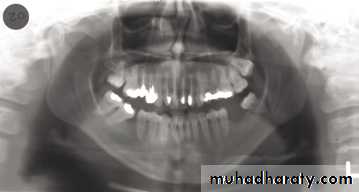

In a good panoramic radiograph:

The mandible is “U” shaped.

The condyles are positioned about equal distance from the inside edges of the image and 1⁄3 of the way down from the top edge of the image.

The occlusal plane exhibits a slight curve or “smile line,” upwards.

The roots of the maxillary and mandibular anterior teeth are readily visible with minimal distortion.

Magnification is equal on both sides of the midline.